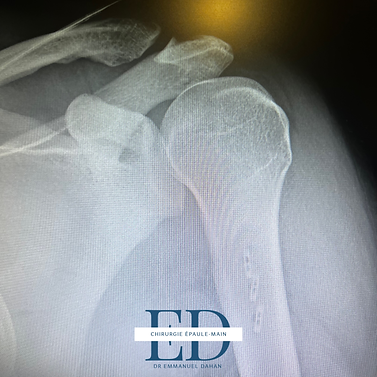

Radiologie post opératoire d'une réinsertion du grand pectoral sur endobouton